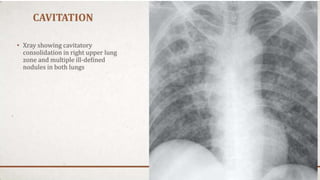

F-Lung Fields

• Normally, there are visible markings throughout the lungs

due to the pulmonary arteries and veins, continuing all the

way to the chest wall.

• Both lungs should be scanned, starting at the apices and

working downward, comparing the left and right lung fields

at the same level.